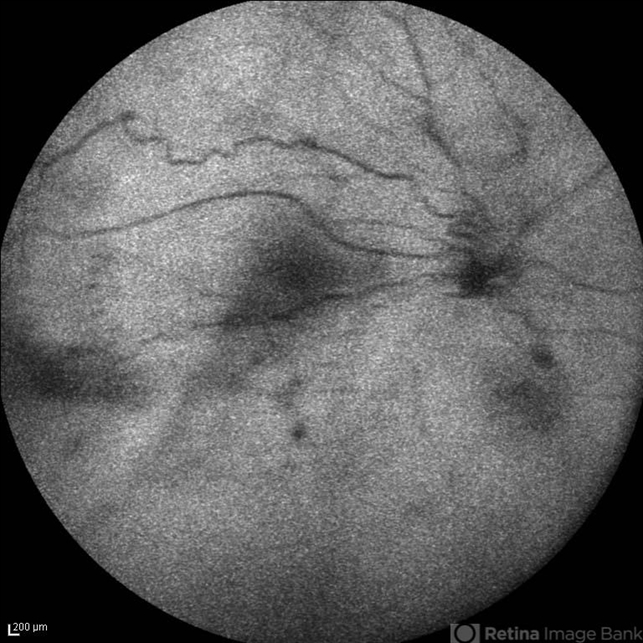

- familial exudative vitreoretinopathy (FEVR), optic disc hypoplasia, autofluorescence imaging

- Autofluorescence imaging of the right eye of a 24-year-old woman with FEVR and optic disc hypoplasia; visual acuity of 20/50. Her brother and sister were also involved with the same ocular disorder.